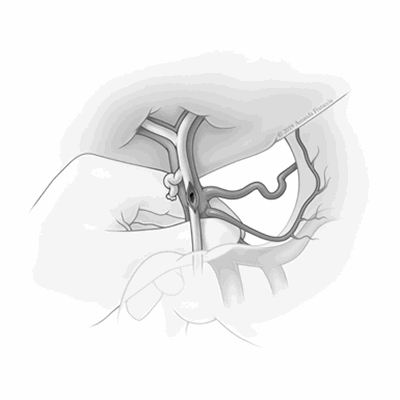

Intraoperative findings during the liver transplantation revealed diffuse inflammatory changes at the hepatic hilum yielding the extra-hepatic portal vein and bile duct inseparable. The common bile duct was first incised, and the metallic stent visualized. Following manual stent extraction, rapid bleeding was temporarily controlled with digital compression of the portal vein at the level of the duodenum. A 1 cm porto-biliary fistula was identified on the posterior wall of the common bile duct (Figure 2).

Figure 2. Porto-biliary fistula in situ. ©2019 Amanda Frataccia. Image used with permission